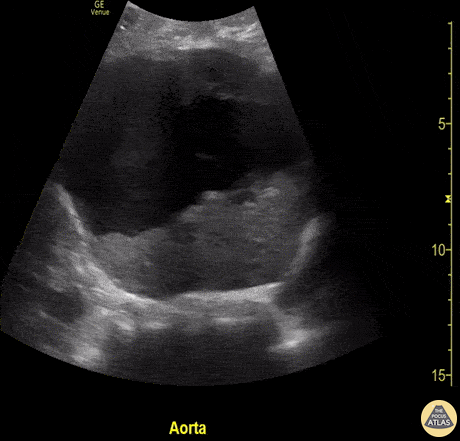

Aorta - Abdominal Aortic Aneurysm

A 72-year-old male presented as a trauma alert and was incidentally identified as having an asymptomatic abdominal aortic aneurysm (measuring 10 cm in diameter). Brian Toston. Internist. Aventura, Florida